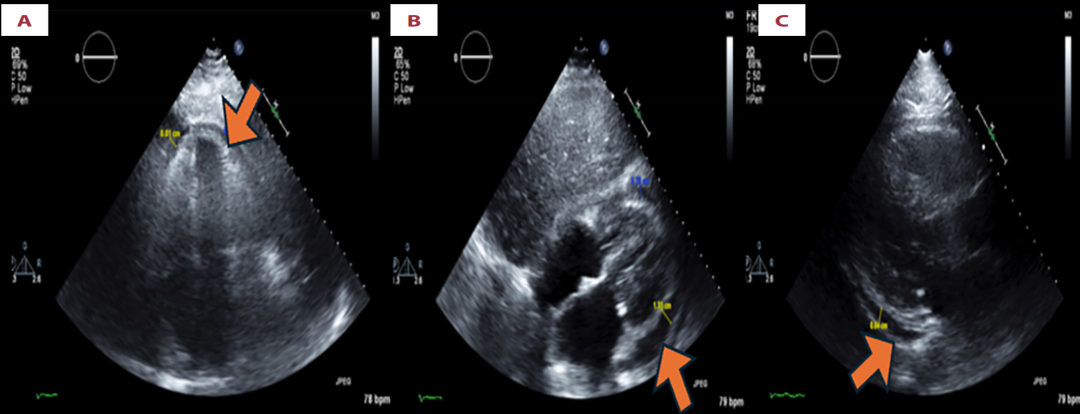

Repeat transthoracic echocardiogram shows a reduction in pericardial effusion, as seen in the apical four-chamber view (A), subcostal view (B), and parasternal long-axis view (C), with the effusion indicated by brown arrows in each image.

在停用阿哌沙班5天后,又进行了左侧胸腔穿刺,引流出1400ml血性浆液性液体,红细胞计数显著下降至34,000/μL。胸水从明显血性向血性浆液性的转变,表明胸膜腔内出血减少,活动性出血已停止,与阿哌沙班停药在时间上高度相关(Naranjo评分6分,提示很可能相关)。他的呼吸困难在胸腔引流后显著改善。心包积液也在未行心包穿刺的情况下自行吸收好转。